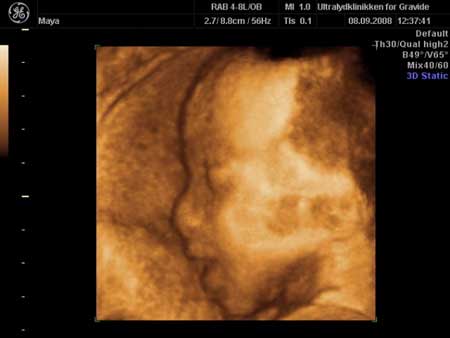

3D scanning – se baby i maven under graviditeten

3d scanning uge 26

3d scanning – uge 26